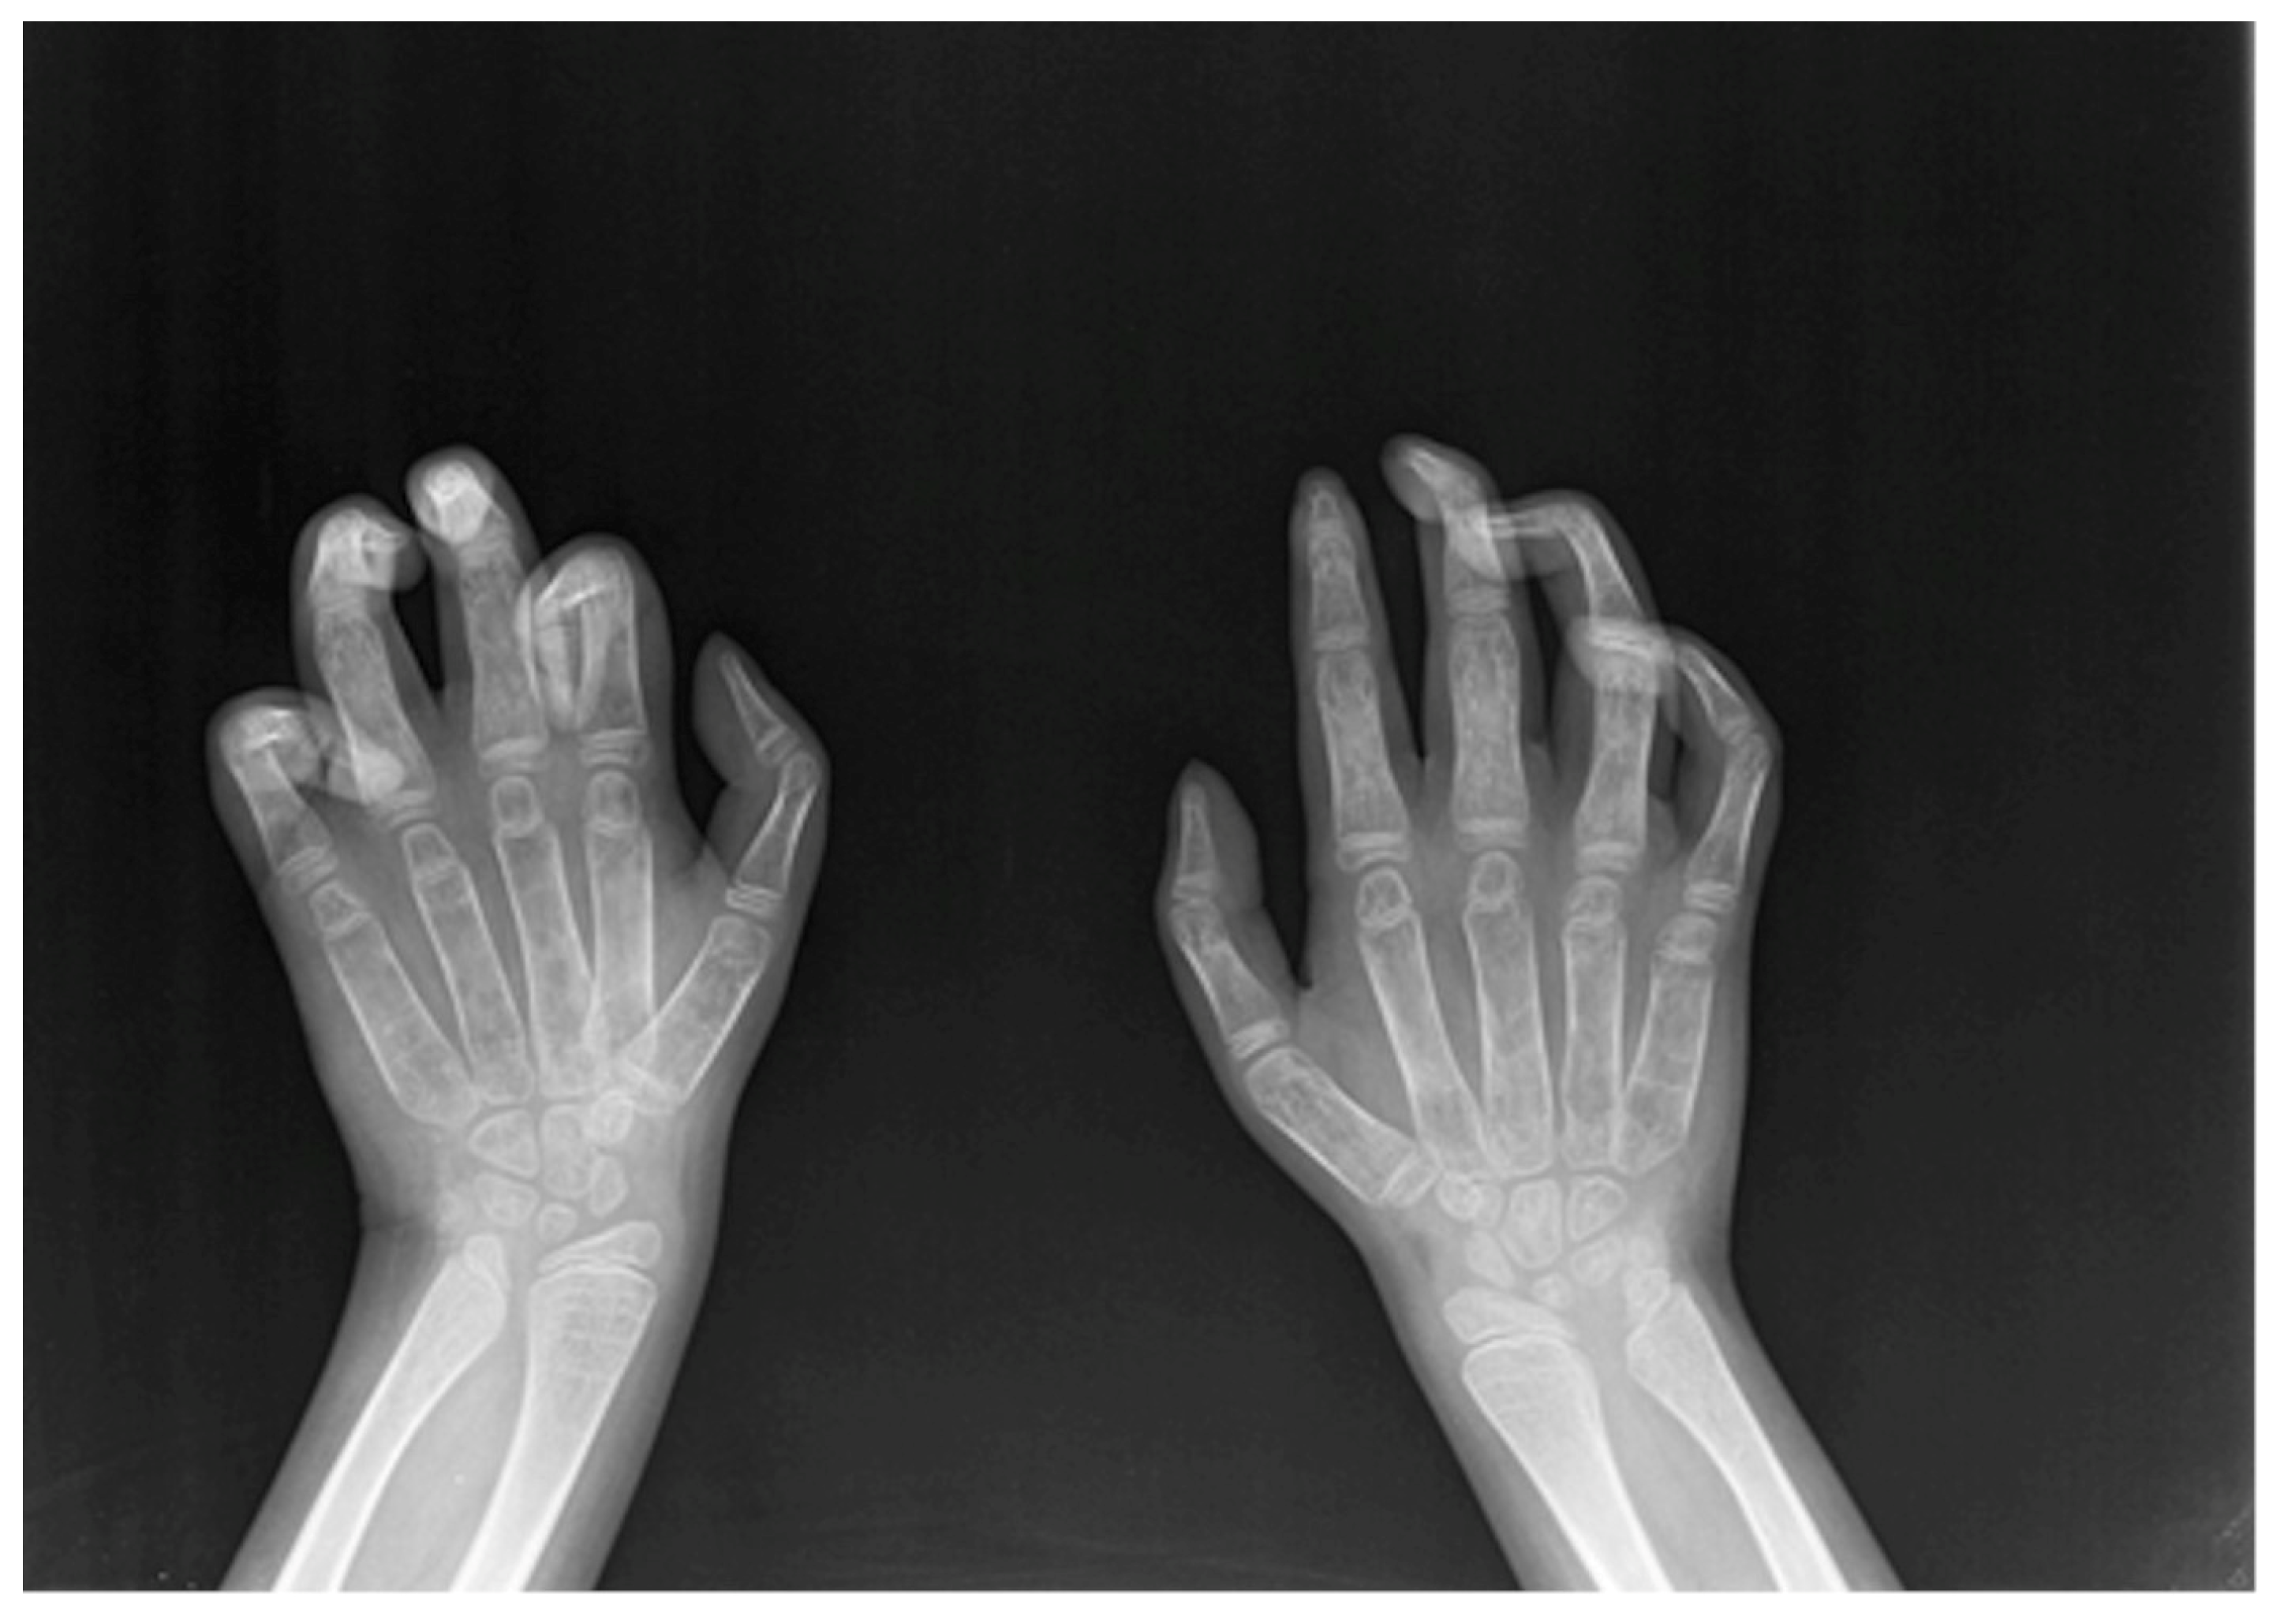

A flexion contracture of the fingers, especially the distal interphalangeal joints, commonly defined as “claw hand”, represents one of the most frequently reported findings among MPS Ia patients.

As paediatric endocrinologists often prescribe a hand–wrist X-ray to assess bone age in children with impaired growth, MPS I-specific radiologic signs, such as bullet-shaped metacarpal bones (“bullet sign”), “claw hand”, clinodactyly (Figure 1), and “pseudo-Madelung” deformity of the distal radius should be promptly recognized by a skilled radiologist. Given the milder MPS Ia bony involvement, the above-mentioned findings may be attenuated and the clinical suspicion should be raised by slighter signs, such as isolated delayed ossification of the carpus, short metacarpal epiphyses, thickened wide and irregular metacarpals, and thickened phalanges [14].

Figure 1. Claw hand and clinodactyly of the left II, III, IV, V finger and clinodactyly of the right III, IV, V finger.